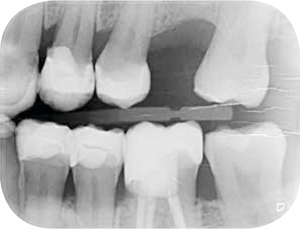

Röntgenonderzoek

Röntgenologisch onderzoek laat meerdere problemen zien. Onder andere een forse zwarting apicaal van element 12 met het beeld passend bij periapicale problematiek en een verleden van apicale chirurgie (afbeelding 8-12 ).

Afb. 9-10

Solo-opnamen van het 1e en 3e kwadrant.

Afbeelding vergroten Afbeelding vergroten